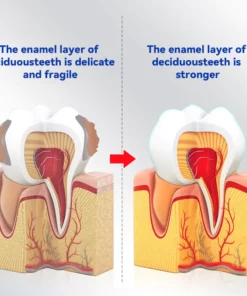

Dental Caries Restoration Process with Oraliz Toothpaste

Image 1: This scanning electron microscope image shows cariogenic bacterial plaque attached to a tooth surface. After 15 days of use, the toothpaste effectively removes this bacterial plaque.

Image 2: This scanning electron microscope image shows a tooth structure affected by caries. Once bacterial plaque is removed, the toothpaste can promote the growth of enamel crystals at a rate of 3-7 microns per day, which can help fill the cavity. With continued use of the toothpaste, the crystals continue to grow.

Image 3: After using the toothpaste for 3-6 months, the enamel crystals can grow up to a thickness of 1-3 millimeters, gradually covering and reducing the cavity, which may help alleviate toothache.

Image 4: The toothpaste’s phosphorus calcium crystals can grow on the collagen fiber chain structure between the molecules of the caries-affected tooth, which can help repair the cavity.

Image 5: This scanning electron microscope image shows repaired enamel crystals in a tooth affected by caries after 8 months of using the toothpaste. The enamel crystals can grow up to a thickness of 1.5-3 millimeters, effectively repairing the cavity and reducing the likelihood of toothache and tooth decay.

Image 6: In this image, the cavity is filled with mineralized streaks of brown-colored crystals, indicating that the cavity has self-healed. The texture is smooth and hard upon probing, marking the end of the tooth decay process.